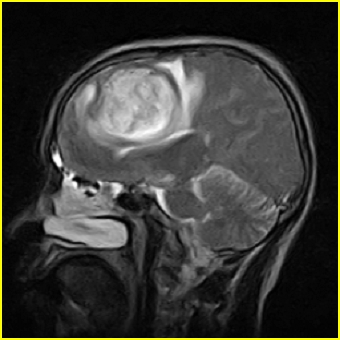

男,45岁,头部剧烈疼痛伴呕吐5天。

右侧额叶见较大的类圆形长t1信号环绕等t1环影,长t2信号环绕短等t2环,周围见明显水肿占位征,中线结构左移,男,45岁,头部剧烈疼痛伴呕吐5天。

右侧额叶,见一占位病灶,t1像病灶、水肿长t1;其间为短t1环行信号。t2像病灶、水肿长t2,其间为短t2环行信号。占位效应明显,中线左移,右测脑室受压闭塞。结合患者发病较急。首先考虑:右侧额叶脑脓肿形成。鉴别:1、转移瘤,多发多见2、胶质瘤。建议增强

t1加权肿瘤呈低信号,肿瘤壁呈等信号.t2 加权时肿瘤呈高信号,肿瘤壁呈等信号.

考虑1脑脓肿.2恶性胶质瘤.